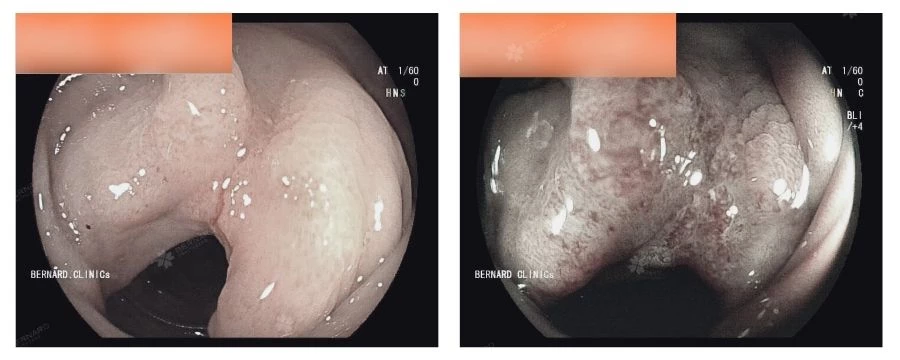

Bệnh nhân tiếp tục được thực hiện nội soi tiêu hóa trên và toàn bộ đại trực tràng để quan sát rõ hơn tổn thương. Từ đây, một tổn thương đáng lo ngại tại đại tràng sigma với đặc điểm co kéo, thâm nhiễm lan tỏa, chiếm gần hết chu vi lòng ruột đã được phát hiện. Theo đúng quy trình, tổn thương được tiến hành sinh thiết để đánh giá chính xác bản chất.